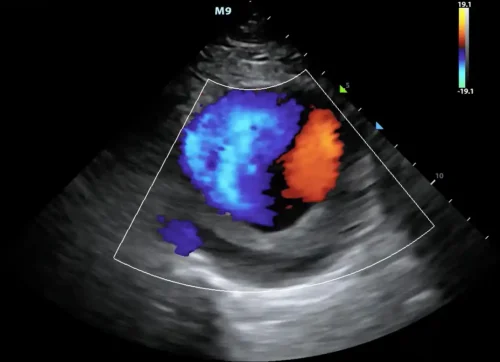

در این روش، دستگاه اکو با استفاده از کدگذاری رنگی، جریان خون را روی تصویر قلب نمایش میدهد. معمولاً رنگ قرمز نشاندهندهٔ جریان به سمت پروب و رنگ آبی نشاندهندهٔ جریان دور از پروب است. رنگهای ترکیبی مانند زرد و سبز نیز میتوانند نشانهٔ سرعتهای بالا یا جریانهای آشفته باشند. این نمایش رنگی به پزشک کمک میکند تا الگوهای جریان را در یک نگاه تشخیص دهد و ناهنجاریها را سریعتر شناسایی کند.

در این روش، رنگها معنایی فیزیکی و دقیق دارند. جریان خونی که بهسوی پروب حرکت میکند، معمولاً با رنگهای گرم—اغلب قرمز—نمایش داده میشود و جریان دورشونده با رنگهای سرد—عمدتاً آبی. این تقسیمبندی، نه قراردادی دلخواه، بلکه بازتابی از تغییر فرکانس امواج بازتابشده است. هرچه سرعت جریان بیشتر باشد، شدت رنگ نیز افزایش مییابد و طیفی از رنگهای روشنتر یا تیرهتر پدید میآید. بدینسان، رنگها نهتنها جهت، بلکه شدت جریان را نیز بازمیتابانند.

اما تفسیر رنگها تنها به تشخیص جهت و سرعت محدود نمیشود. یکی از پدیدههای مهم در داپلر رنگی، Aliasing است؛ حالتی که در آن سرعت جریان از حد قابل اندازهگیری دستگاه فراتر میرود و رنگها بهصورت وارونه یا موزاییکی دیده میشوند. این پدیده، هرچند در ظاهر نوعی اختلال است، اما در بسیاری موارد نشانهای از جریانهای پرسرعت و غیرطبیعی است؛ مانند نارسایی شدید دریچهای یا تنگیهای مهم. پزشک آگاه، این وارونگی رنگ را نه خطا، بلکه نشانهای بالینی میداند و آن را در تحلیل خود بهکار میگیرد.

جریانهای آشفته یا Turbulent Flow نیز در داپلر رنگی جلوهای خاص دارند. این جریانها، که معمولاً در اثر تنگیها، ناهنجاریهای مادرزادی یا نارساییهای شدید پدید میآیند، با رنگهای درهمتنیده و موزاییکی نمایش داده میشوند. این آشفتگی رنگی، بازتابی از بینظمی سرعت و جهت خون است و میتواند پزشک را به وجود اختلالی مهم در مسیر جریان رهنمون سازد. در مقابل، جریانهای طبیعی و آرام، الگویی یکنواخت و همگن دارند و رنگها در آنها بهصورت منظم و پیوسته دیده میشوند.

در دریچهها، هر رنگ و هر الگو معنایی خاص دارد. در دریچهٔ میترال، جریان طبیعی در زمان دیاستول بهسوی بطن چپ است و با رنگی مشخص دیده میشود. هرگونه جریان بازگشتی در زمان سیستول، که با رنگی مخالف ظاهر میشود، نشانهٔ نارسایی است. در دریچهٔ آئورت، جریان طبیعی در زمان سیستول بهسوی آئورت است و هر جریان معکوس در دیاستول، نشانهٔ نارسایی آئورت. این الگوهای رنگی، همچون امضایی برای هر بیماریاند و پزشک با شناخت آنها میتواند شدت و ماهیت اختلال را دریابد.